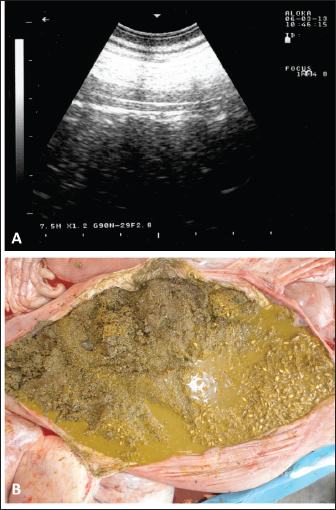

Fig. 7. Ultrasonographic and postmortem findings in an adult female camel with a history of pica and decreased fecal output and abdominal distension. Image (A) was taken using a 3.5 MHz sector transducer and shows sonography of the rumen from the left lower abdomen where several pin-points acoustic shadowing were imaged. Image (B) shows large amounts of sand within the rumen detected at postmortem examination.

Sonographic and postmortem findings are summarized in Table 2. In cases of camels presented with a history of pica and with decreased or total absence of feces, the obstructing foreign body was imaged in 10 of the 25 camels (40%) occluding completely or partially the intestines that may be confirmed at abdominal surgery (Figs. 2, 3, and 6). Foreign bodies within the rumen could not be visualized with ultrasound owing to the gas content. In cases where the rumen is impacted by sand, small pin-points revealing acoustic enhancement were imaged in 5 (20%) of the camels. An example of these cases is shown in Figure 7. Foreign bodies were removed from the rumen or intestines at exploratory rumenotomy and laparotomy, which included plastics, cloths, sand, mud, robes, wool balls, glasses, or even metallic objects that were blunt or sharp (Figs. 8 and 9).

During the past 13 years, our research group has focused on the effectiveness of diagnostic imaging techniques in dromedary camels either in the healthy or diseased conditions (El-Tookhy and Tharwat, 2012; Ali et al., 2018; Al-Sobayil et al., 2018; Tharwat et al., 2012a,b,c,d; Tharwat, 2013a; Tharwat et al., 2013; Tharwat and Al-Sobayil, 2016a; Tharwat et al., 2018a; Tharwat, 2019; Tharwat, 2020a,b,c; Tharwat, 2021a,b; Tharwat and Al-Hawas, 2021; Tharwat and El-Tookhy, 2021; Tharwat et al., 2021; Tharwat and Al-Hawas, 2023; Tharwat et al., 2023; Tharwat,$ 2024; Tharwat and Al-Hawas, 2024). In these studies, the occluding foreign body was imaged obstructing the intestines either partially or completely. Because of the gaseous contents, the foreign bodies could not be localized within the rumen. However, in camels with rumen sand impaction, shining pin-points with acoustic enhancement are clearly visualized.